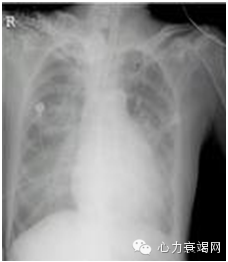

肺水肿表现